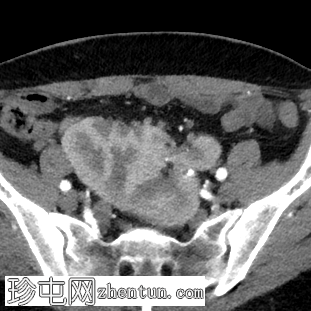

轴位增强扫描

动脉期

双肾位于盆腔中线,由一条宽阔的肾实质带从上极延伸至下极,融合在一起,形似煎饼肾。

该变异肾由七条肾动脉供血,其中三条独立起源于腹主动脉下段(IMA)下方,其余四条分别两两起源于两侧髂内动脉(IIA)。

两条独立的输尿管从前方开口,以正常位置进入膀胱。

另发现脾动脉假性动脉瘤伴新月形壁内血栓。